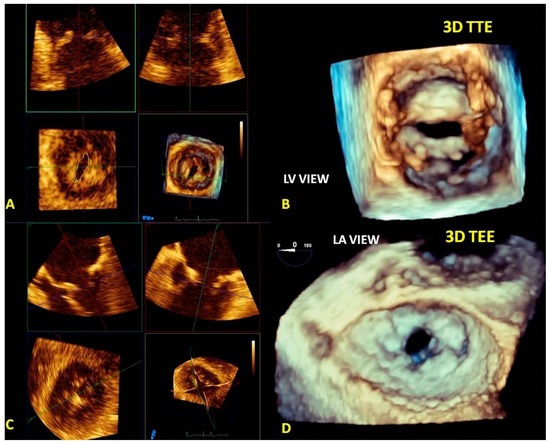

3.4. Quantification of MV Stenosis